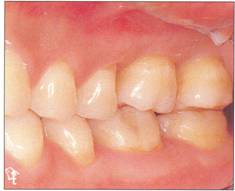

Fi 545e45f gs 5-2p and 5-2q Two years 5 months after transplantation. The donor tooth is restored with composite resin. |

Restorative treatment Unnecessary tooth reduction can be avoided by careful restorative treatment planning (see Fi 545e45f gs 5-1, 5-4, and 5-6). Surgical procedure |